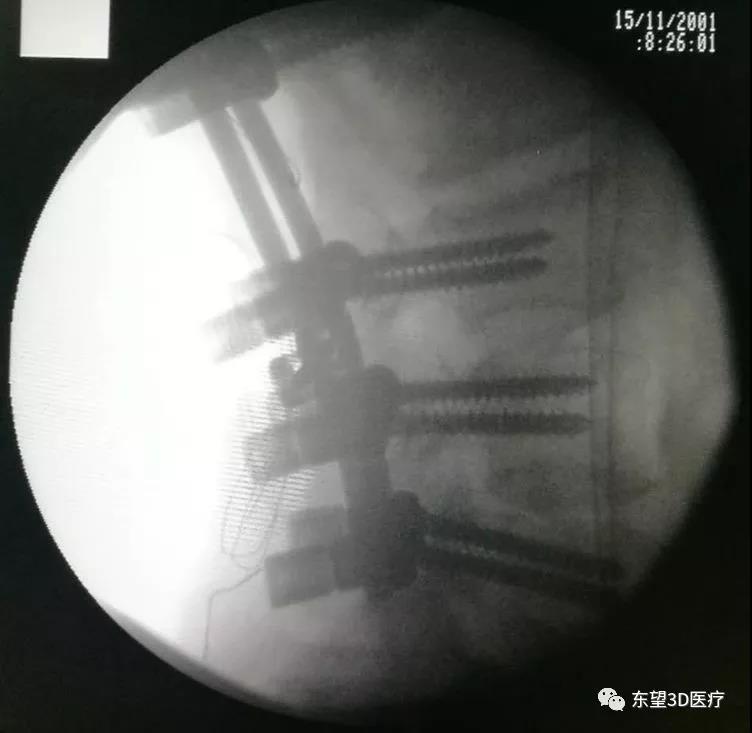

術中置釘、減壓見硬膜囊脊髓搏動良好

X線透視椎弓根釘位置準確